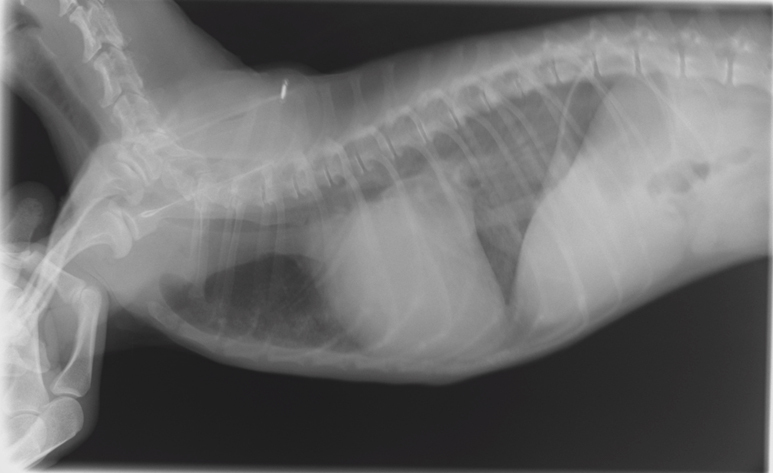

| 検査 | 身体検査、聴診、レントゲン検査、超音波検査、心電図検査、血圧測定、血液検査 |

症状や検査結果を基に、薬の種類や量を決めていきます。また、病状の進行によって種類、量が変わるので、定期的な検査をします。

心臓病の検査で特に大きな要となるのが、超音波検査でありますが、大変高い技術が求められる検査であります。この技術により診断が左右することも大いにあります。当院では幅広い知識と高い技術で検査を行い、診断しております。この検査では、動物に横になったり、仰向けになったりしてもらいますが、その姿勢が苦手な子、またその姿勢によって息苦しくなってしまう子に対しては、立ったままの姿勢での検査を行っております。